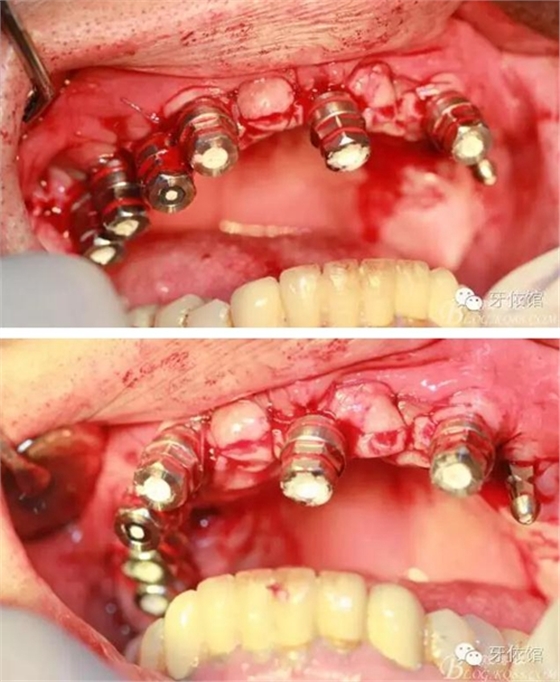

降低骨高度,左右1,2骨寬度嚴(yán)重不足,決定將前牙2——2區(qū)間植體植在切牙孔內(nèi)

左右3牙位分別植入一顆

其余牙位也分別將植體植入

去除多余軟組織

將攜帶體重新與植體連接